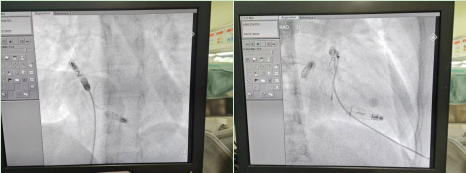

本次手术患者是一位 35 岁年轻女性,临床诊断为高度房室传导阻滞、先天性房间隔缺损。患者既往有阵发性房颤消融病史,以及右心室无导线起搏器植入史。经过医疗团队全面评估,该患者符合 AVEIR™ DR 双腔植入式无导线心脏起搏系统的植入指征,且无明显禁忌症。在与患者及其家属充分沟通后,团队决定施行 AVEIR™ DR 双腔植入式无导线心脏起搏系统的植入手术。

陈琦教授介绍:「手术分别在患者右心耳基底部和右心室低位间隔处植入一枚无导线起搏器,两者通过 i2i™通信技术进行配对,实现房室顺序起搏。该起搏系统支持灵活选择起搏模式,既可针对患者当前病情实施治疗,也为未来可能的病情进展预留了干预空间。」